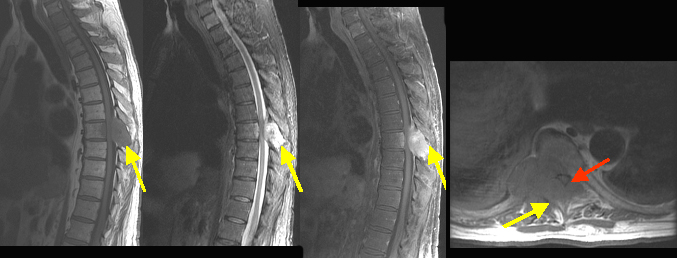

| Pre-contrast sagittal T 1 wtd. MRI of the thoracic spine | Sagittal T 2 wtd. MRI | Post contrast sagittal T 1 wtd. MRI | Pre contrast axial T 1 wtd. MRI |

Bony metastasis from renal cell carcinoma with epidural tumor producing cord compressionFindings: Bony metastasis involving the T 8 vertebral body, right pedicle/transverse process and spinous process (arrow in A,B,C,D) with epidural tumor producing marked degree of cord compression (red arrow). |